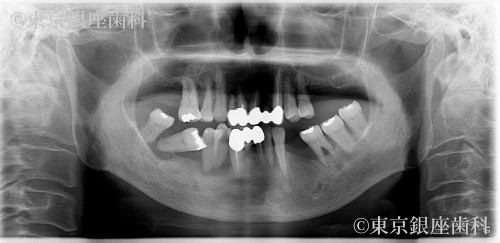

After

重度歯周病で上下インプラント治療を実施。術後に皮膚の湿疹・赤みが出たが、チタンアレルギーではなく経過観察で改善。現在も問題なく使用できている。

上下ワンデイインプラント